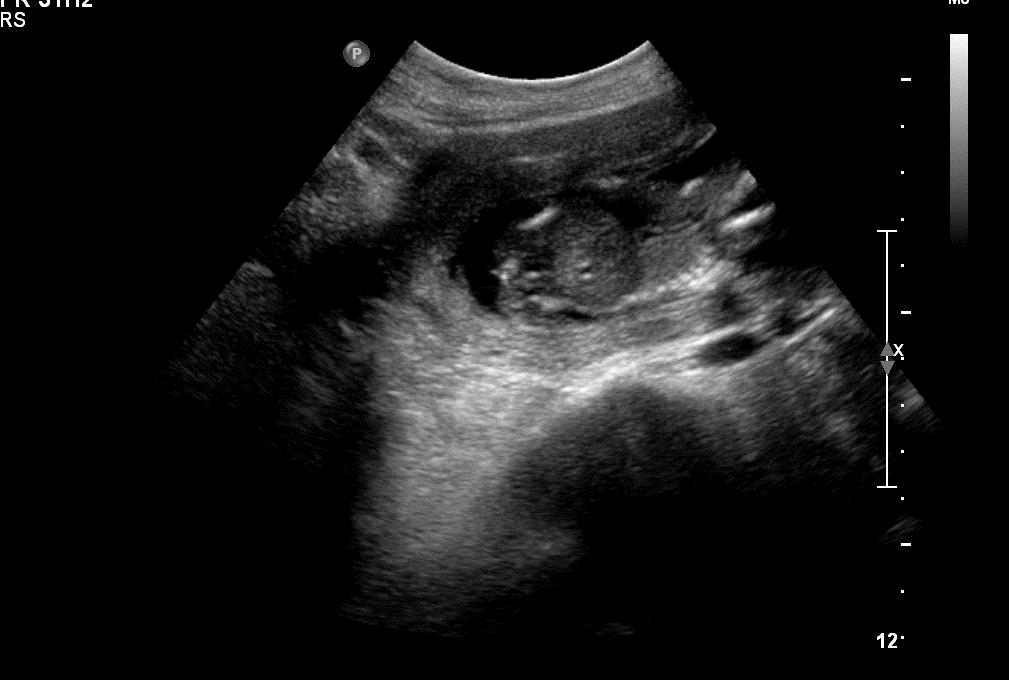

Attachment 3356Attachment 3357

Sono says, "GIRL?" But what's that in the middle?

I can't figure out what I am seeing.

I'm guessing the far left of the photo is where the sex is. It's not a potty shot but between the legs. However, we had a gender party yesterday. So, we never saw the sono explain their reasoning - just was told it was a girl.

I think we're seeing the baby's spine. The sono saw way more than we're seeing right here. What you could be seeing now could be a foot. I think you're good if they said girl :) Congratulations!!

Where is a potty shot? I would have guessed boy by the last shot.

True...didn't you get a potty shot, since this was for a private gender reveal?

Maybe boy?